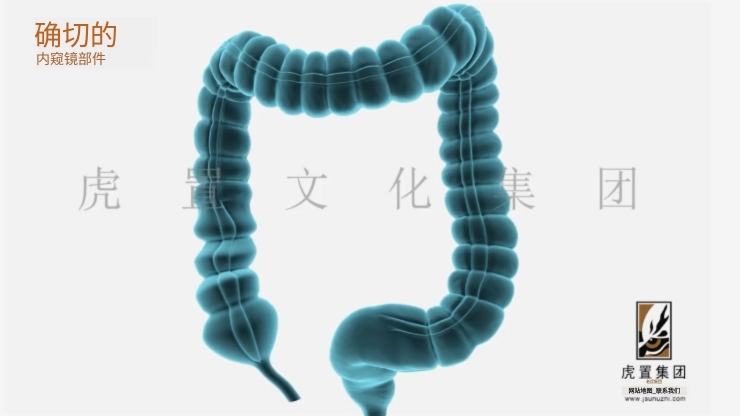

- > 医疗三维动画用到哪些技术-虎置文化集团2026-03-18

- > 医疗器械三维动画怎么收费-虎置动画2026-03-17

- > 医学手术动画有哪些优势-虎置文化集团2026-03-02

- > 医学三维动画都有哪些优势-虎置动画制作2026-02-06

- > 怎么制作医疗三维产品动画视频-虎置动画2026-01-23

- > 医疗设备动画的作用主要有哪些-虎置动画2026-01-16

- > 医学三维动画有哪些特点和优势-虎置动画2026-01-13